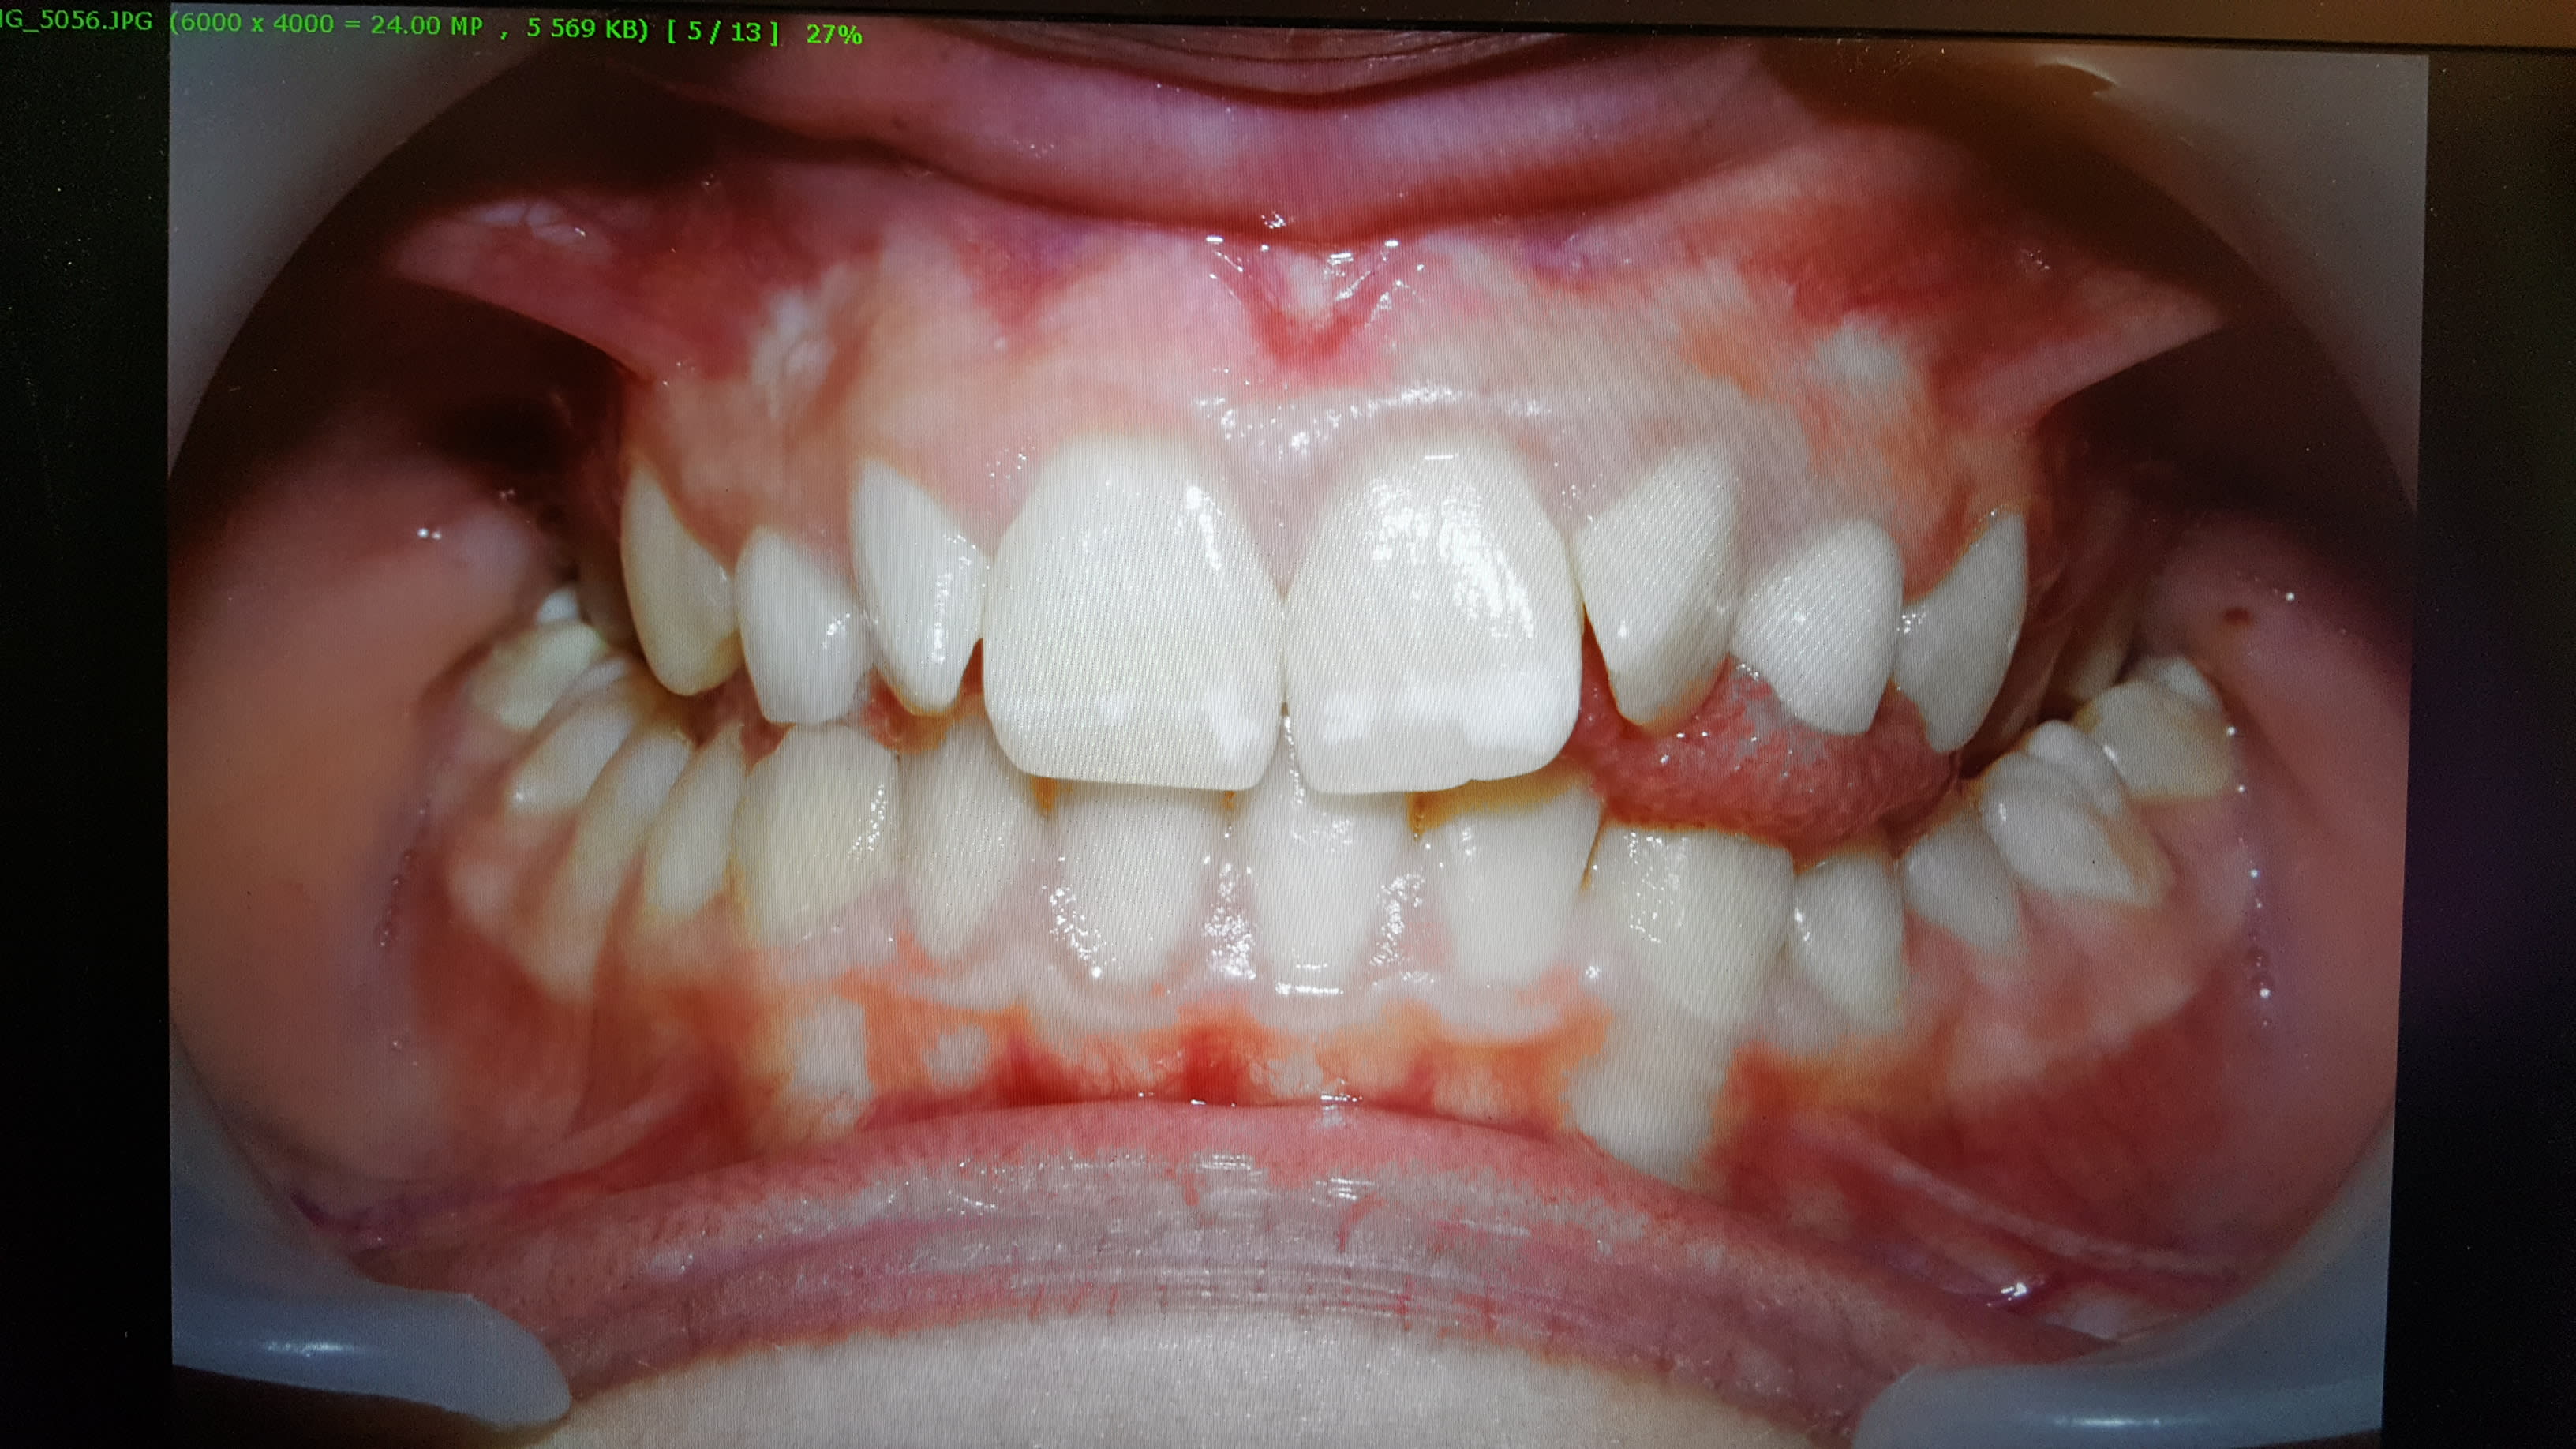

je voudrais savoir avec quelle logiciel (gratuit) faites vous vos présentations de cas

D'autres part sur les photos j'ai toujours les joues dans les secteurs molaires, une solution à me proposer?

Pour ma part j utilise fastone image viewer pour tout ce qui est recadrage et luminosité. Puis PowerPoint.

Pour ce qui est des joues : j ai 4 ou 5 types d écarteur différents. Il faut trouver celui bien adapté au patients (En particulier pour l ortho ou la taille des bouches varie tout le temps).

Après l'astuce que m a fait donné un prof : tu met To doigt sur le flash comme pour le fermer a moitié. Ça permet de mieux diriger le flash sur les dents et pas la lèvre supérieure de ton patient. Excuse pour le rendu de ma photo j ai photographié mon écran.